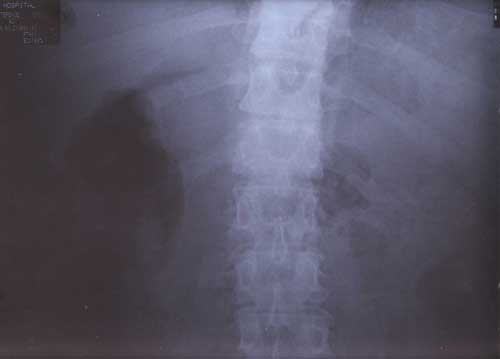

22nd January 2000